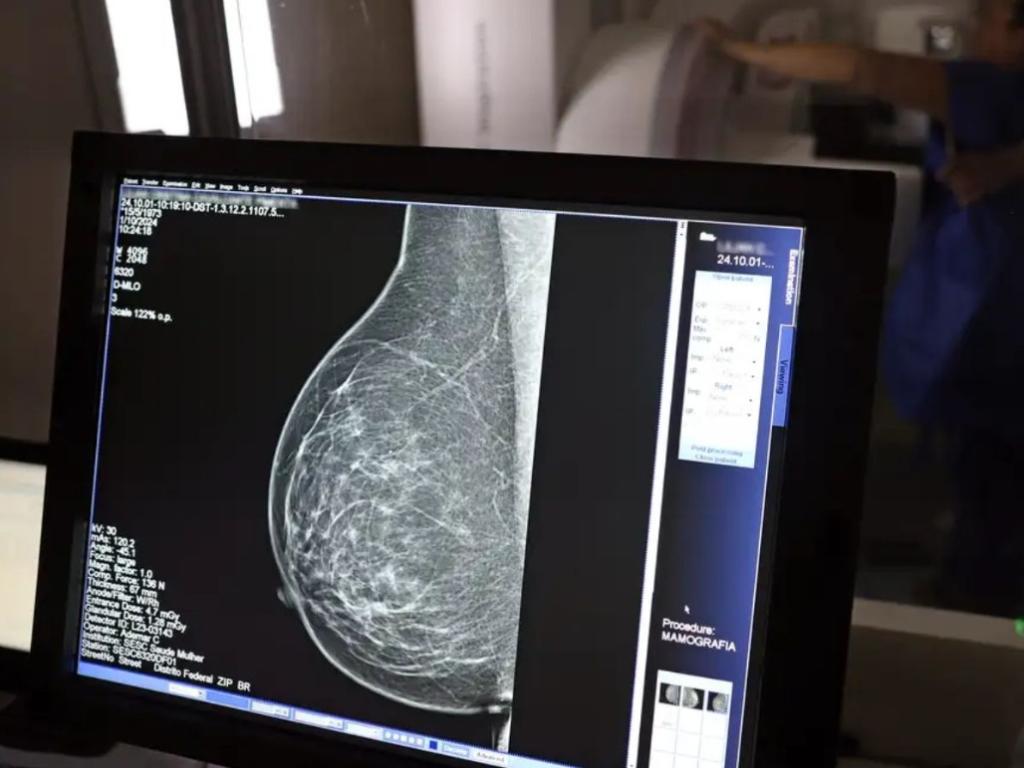

A profissional contou que, ao longo do contrato, foi diagnosticada com câncer de mama

A profissional contou que, ao longo do contrato, foi diagnosticada com câncer de mama. Ela apresentou o atestado médico ao empregador em 2/1/2025, com o registro da doença: neoplasia maligna de mama. Também entregou o relatório médico informando de forma expressa o diagnóstico de câncer de mama direita multifocal.